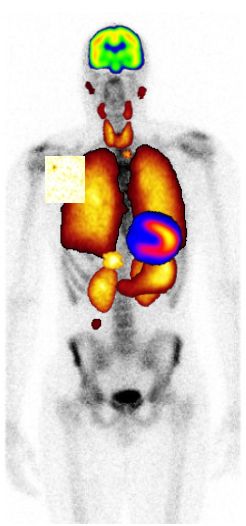

Nukleærmedisin er bruk av åpne radioaktive stoff for diagnostikk og terapi.

Senter for nukleærmedisin og PET ved Haukeland Universitetssykehus er del av Radiologisk avdeling. Vi utfører alle nukleærmedisinske  undersøkelser og terapier i Hordaland. I tillegg har vi regionsansvar for spesielle diagnostiske metoder og landsfunksjon for enkelte nukleærmedisinske behandlingsformer.

Avdelingen er fulldigitalisert. I 2008 har nukleærmedisin flyttet i ett nytt integrert senter for nukleærmedisin og PET. PET-senteret inkluderer et radiokjemisk laboratorium med syklotron til produksjon av de radioaktive legemidlene og et kombinert PET-CT kamera.